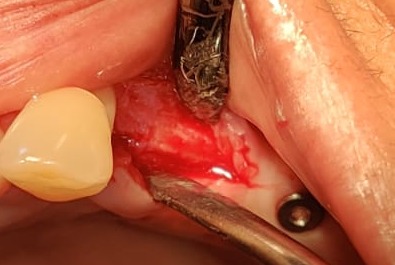

It was really challenging case. Delayed implantation with highly resorbed bone.

It was acid test for osseosure to create osteotomy without fracturing bone. and osseosure did it .

implant went with 40 NCm torque.